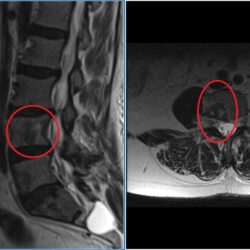

Metástasis vertebrales

Como todos sabemos el cáncer es una de las enfermedades